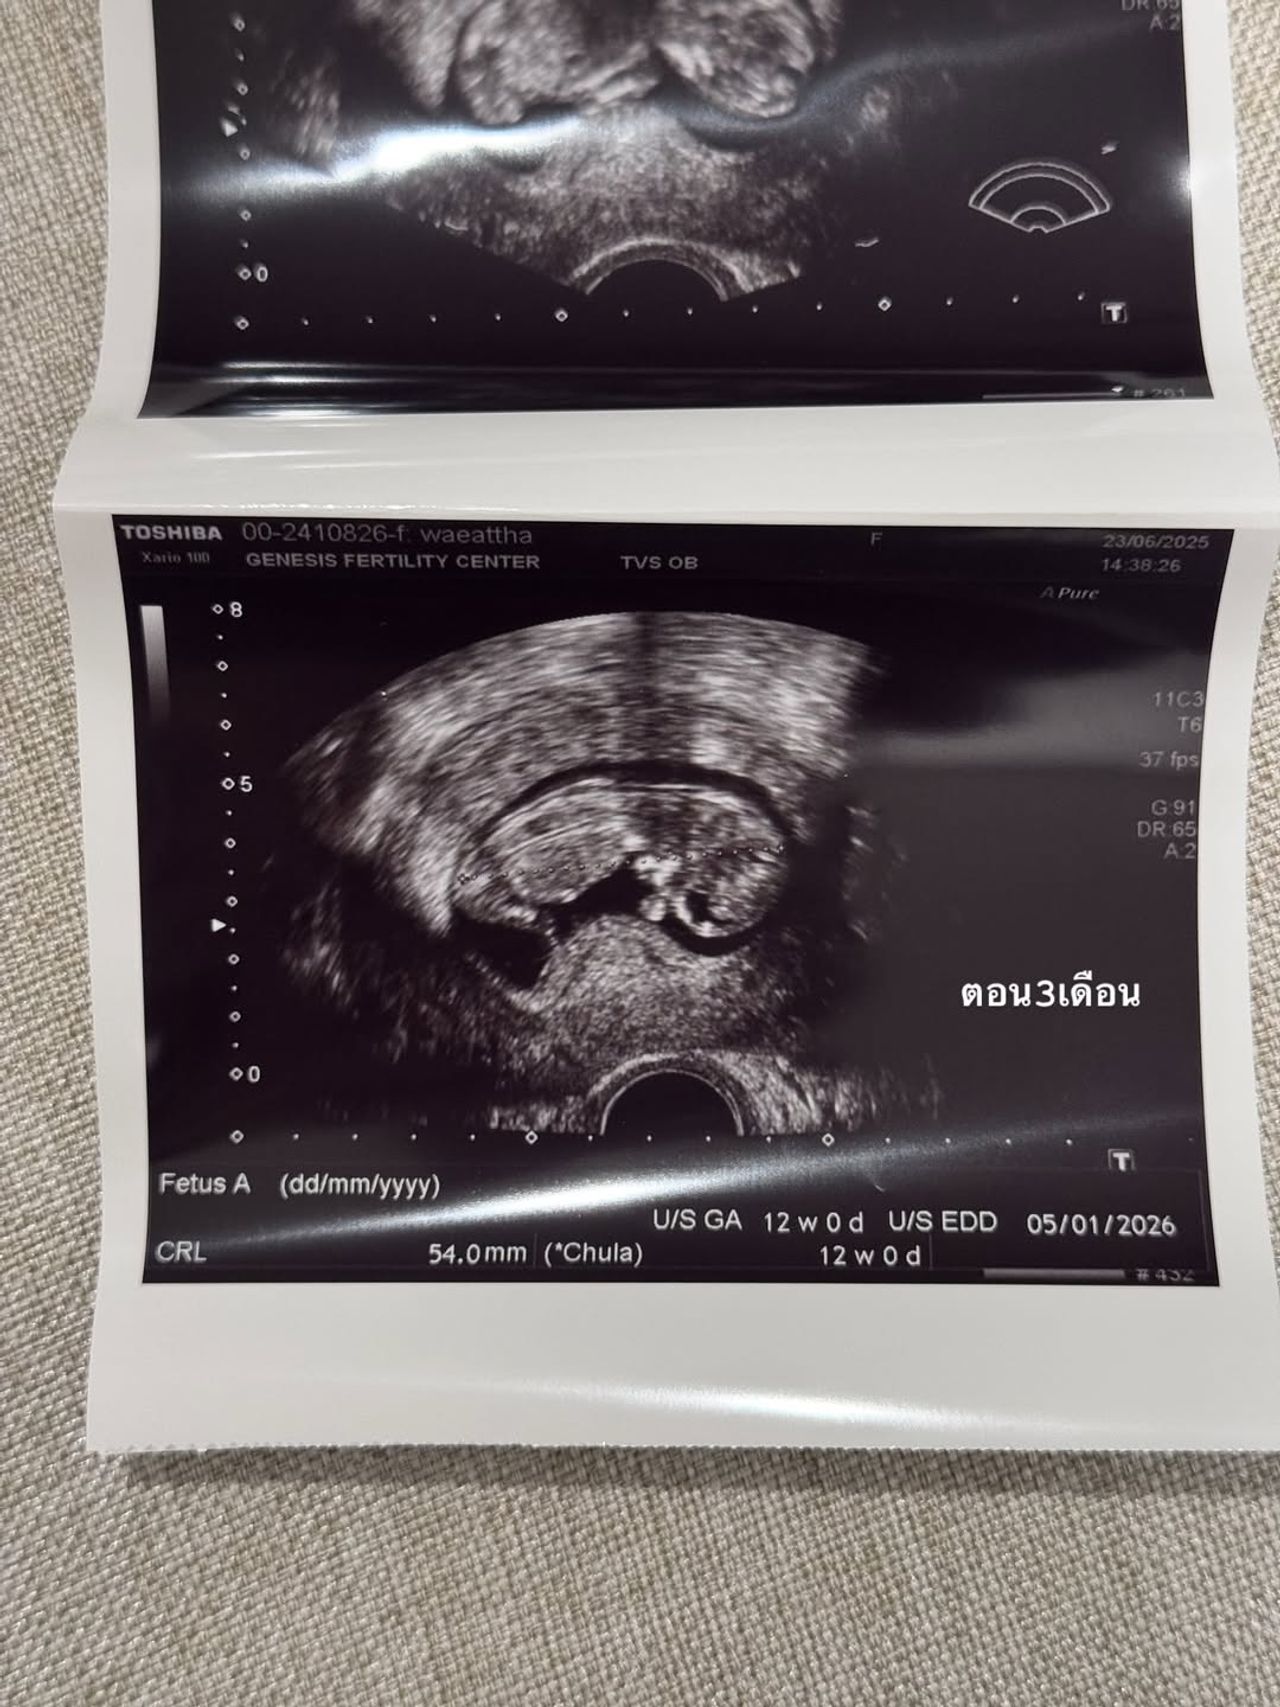

ช่วงนี้หายๆ ไปเพราะว่าเนยมีน้อง ในรูปคือประมาณ 3 เดือน ตอนนี้ก็เกือบจะ 4 เดือน ท้องป่องแล้ว ต้องบอกว่าจะมีลูกคนนึงไม่ง่าย เข้าใจว่าตัวเองแข็งแรงสุขภาพดีมาก ดูแลตัวเองมาอย่างดีมากๆ อาหารการกินคือคลีน ไม่ดื่ม ออกกำลังกายสม่ำเสมอ นอนไม่ดึก แต่ปรากฏว่า เนยสูญเสียน้องไปถึง 2 รอบ จนแปลกใจมากจริงๆ เลยตัดสินใจไปหาคุณหมอ

เนยเลยเลือกใส่ตัวอ่อน เลือกที่จะให้ลูกสมบูรณ์ 100% ขั้นตอนนั้นใช้ความอดทน..55 ไม่เจ็บหรอกแต่จุกจิกเหลือเกิน ต้องกินยา สอดยา ฉีดยาตัวเองให้ตรงเวลาเสมอไปทำงานทำอะไรต้องรีบกลับให้ทันเวลาฉีดยา ตอนนี้น้องสมบูรณ์แข็งแรงมากแค่ 3 เดือนก็ดิ้นเก่งซะแล้ว